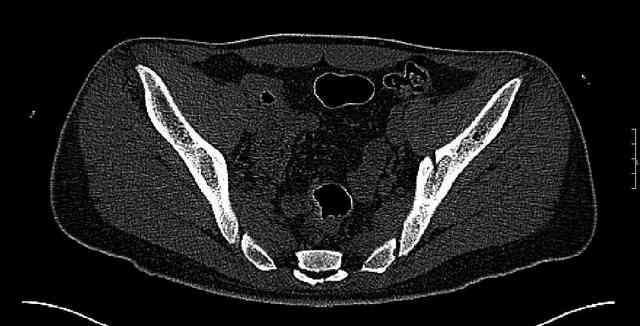

Some more images. Does it help to guess which part of the acetabulum is displaced?

Normal appearing SI joints and a healed posterior column limb... my bet's on caudal segment displacement.

The joint is non-concentric as the head appears to be either "following the caudal segment", or the dome component is displaced from the tethered head... or so it seems... and he's young... so, many fracture surgeons would recommend reduction and fixation.

segment. It's my best guess that it is the caudal portion and there exists a healing fracture line somewhere thru the posterior column...one image

suggests it. If true, its early healing/union should be disrupted, and the resultant fragment mobility then allows accurate reduction.